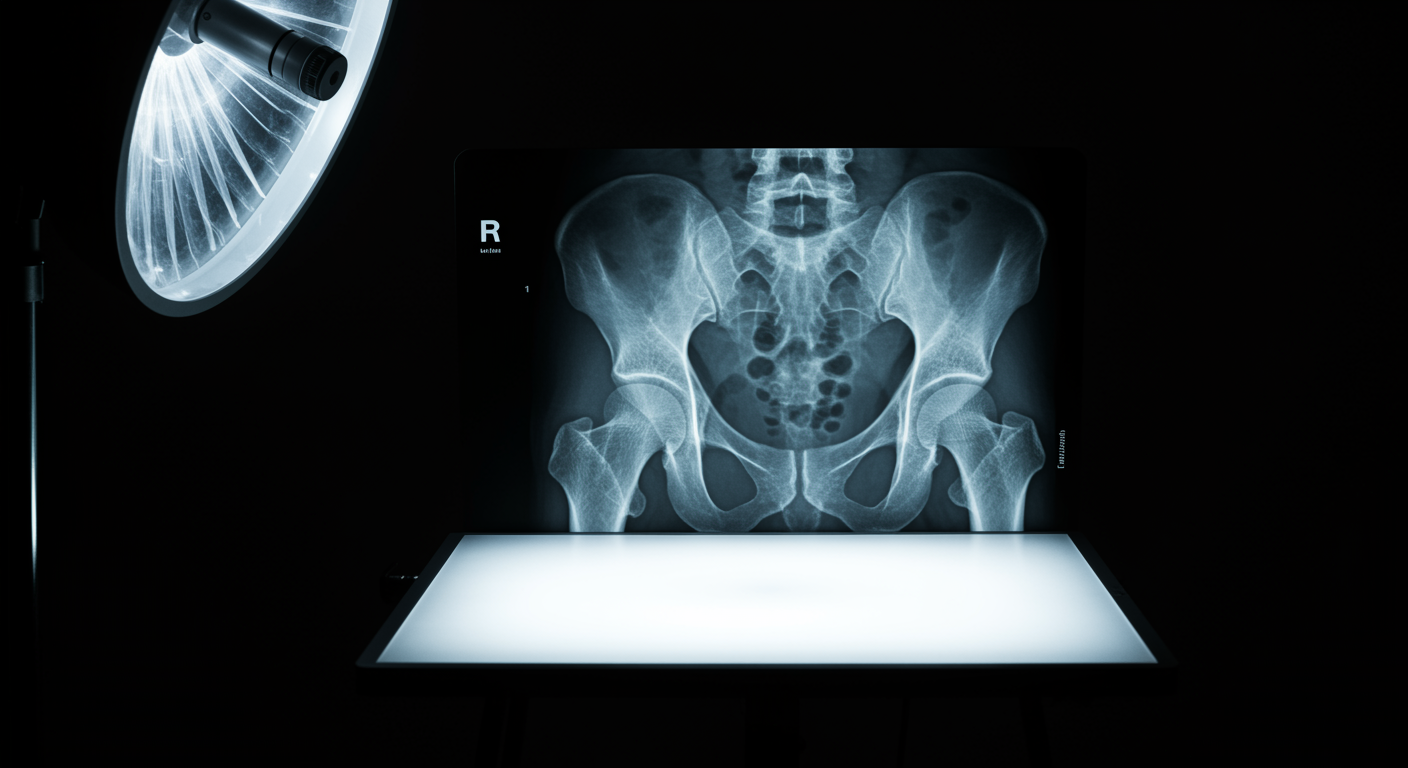

Yes, significantly. This large prospective study found that women who stopped hormone therapy had a 55% increased risk of hip fracture within 3-5 years compared to those who continued treatment. The protective bone effects of hormone therapy are lost relatively quickly after discontinuation, making transition planning crucial for women who need to stop treatment.

This study highlights one of the most important but overlooked aspects of hormone therapy: what happens when you stop. Many women are told to discontinue hormone therapy at arbitrary ages without consideration of the consequences for bone health. The rapid loss of bone protection after stopping hormone therapy means we need better strategies for managing this transition, including bone density monitoring and alternative treatments.